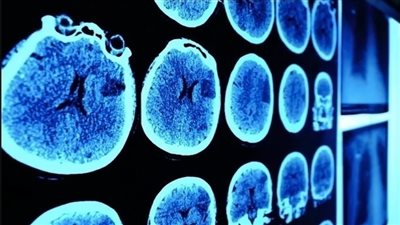

في مفاجأة طبية، تحدى طفل بلجيكي توقعات الأطباء، بعدما شفي تماماً من ورم سرطاني في الدماغ، ليصبح أول طفل في العالم يشفى من هذا النوع من السرطان. وقد شخّص الأطباء إصابة الطفل لوكاس..